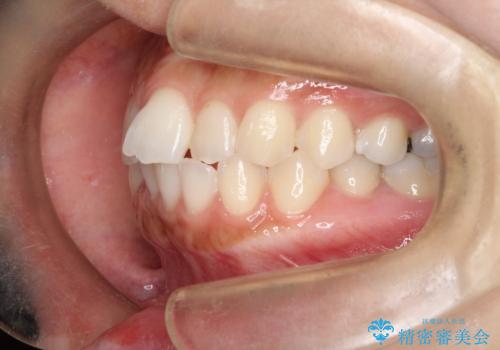

- 口元が出てるのが気になるとのことで来院されました。

上下左右前から4番目の歯を抜歯して前歯を後方に下げて、口元を下げる計画としました。